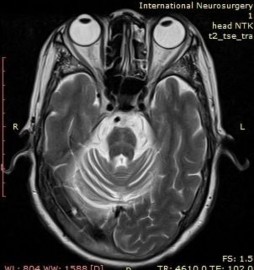

MRI chụp lại lần thứ 2 lúc nhập viện ghi nhận teo cầu não và tiểu não, với dấu hiệu “bánh ngọt chữ thập”.

MRI não ghi nhận teo cầu não và tiểu não với dấu “bánh ngọt chữ thập”